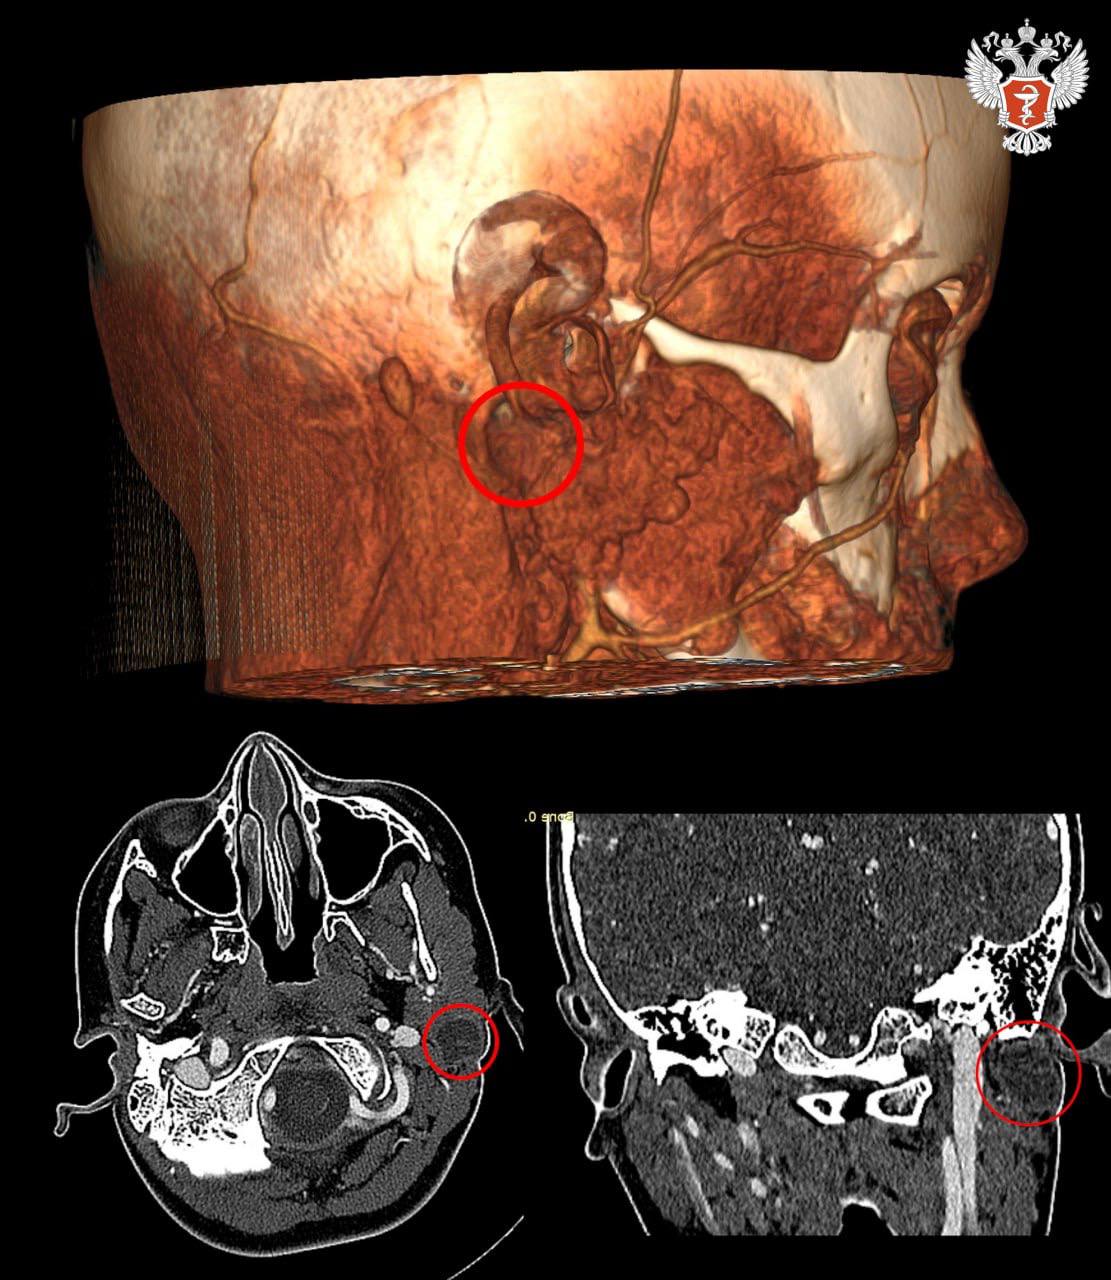

Сложность лечения заболевания обусловлена не только его редкостью, но и анатомическим расположением кисты — в глубине тканей она прилегает к жизненно важным крупным сосудам и лицевому нерву, повреждение которого грозило асимметрией лица и потерей мимики.

В результате врачи удалили кисту через один небольшой разрез за ухом, избежав повреждения всех прилегающих структур. Разрез скрыт в естественной складке за ухом, и на лице ребенка не осталось ни одного видимого шрама.